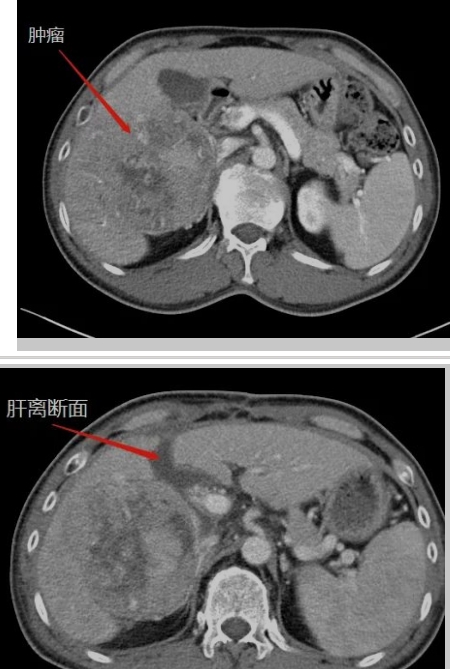

在生命的長河中,每個(gè)人都在與時(shí)間賽跑,與命運(yùn)抗?fàn)帯6鴮ν跬砥诟伟┗颊邅碚f,這場賽跑尤為艱難,這場抗?fàn)幐裢怏@心動(dòng)魄。還記得四年半以前,當(dāng)40多歲的王先生被確診為晚期肝癌伴乙肝、肝硬化時(shí),絕望的陰霾籠罩著整個(gè)家庭。對王先生來說,那是一段黑暗的日子,對未來的恐懼,對生命的不舍,尤其對年幼的孩子的不舍,讓他...